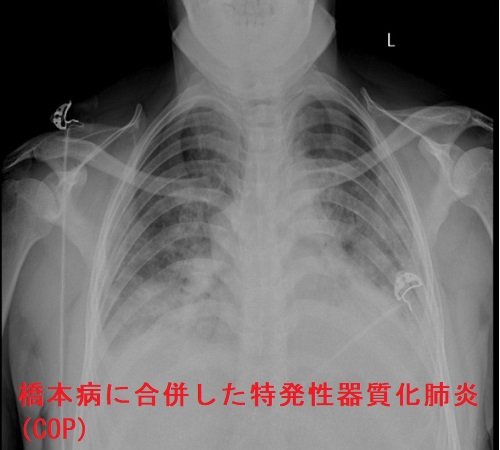

橋本病(慢性甲状腺炎)・バセドウ病と特発性器質化肺炎(Cryptogenic organizing pneumonia; COP)

橋本病(慢性甲状腺炎)・バセドウ病に合併した特発性器質化肺炎(Cryptogenic organizing pneumonia; COP)の報告として、

- 潜在性甲状腺機能低下症/橋本病(慢性甲状腺炎)に合併(Exp Ther Med. 2019 Dec;18(6):4609-4616.)

- 甲状腺機能亢進症/バセドウ病とほぼ同時期に発症・再発を繰り返した(Respiration. 2000;67(5):572-6.)

などのケースがあり、自己免疫反応が原因なのか、甲状腺ホルモン自体が原因なのか不明です。